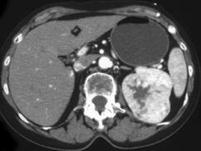

问题 男,54岁,左侧腰痛伴间断性血尿2 月余,请结合CT图像,选择最可能诊断 ( )

选项 A、左侧嗜铬细胞瘤 B、左侧肾盂癌 C、左侧肾血管平滑肌脂肪瘤 D、左侧肾上腺腺癌 E、左侧肾癌

答案 E